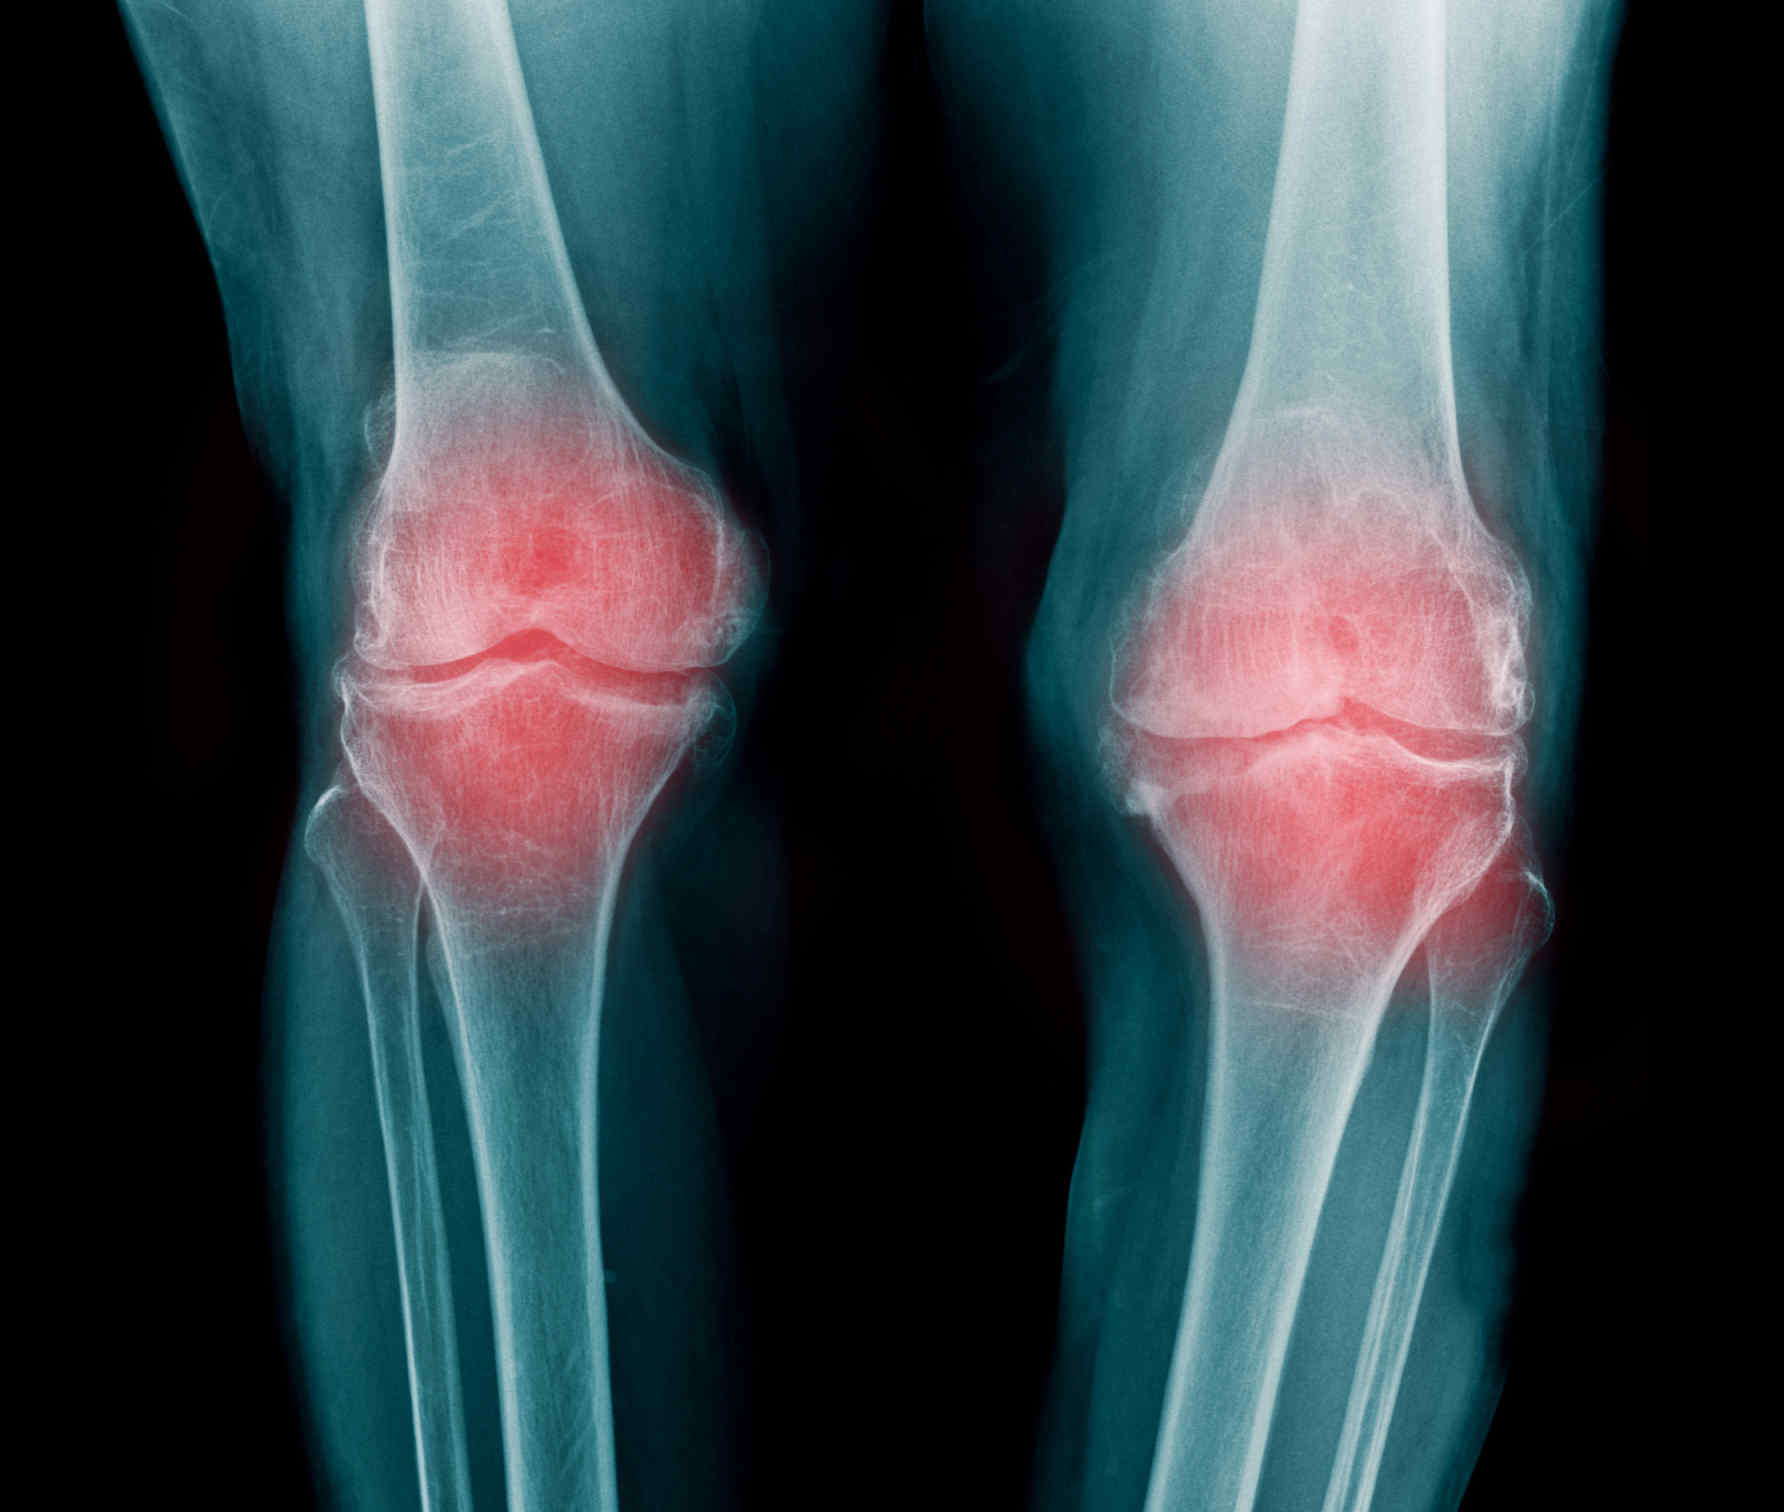

Медицинские состояния: Септический артрит коленного сустава

Раздел: Мир в картинках